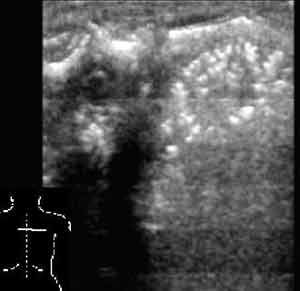

Рис. 8. Пневмония у новорожденного.